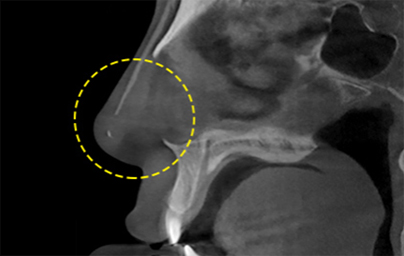

透過立體的骨骼圖進行精準診斷的 3D CT